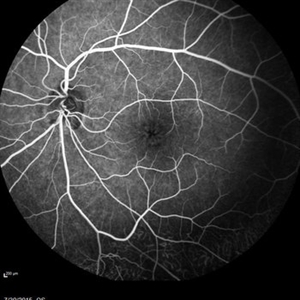

Retinal Dystrophy of 24-Year-Old Male Fill Phase FA OD

Nov 25 2015 by Zach Dupureur

Fluorescein angiography of a 24-year-old male. Juvenile retinoschisis on OCT. FA shows outer retinal staining. Could be associated with Goldmann Farve Syndrome.

Photographer: Zach Dupureur, OCT-C

Condition/keywords: Goldmann-Favre Syndrome, juvenile retinoschisis, retinal dystrophy